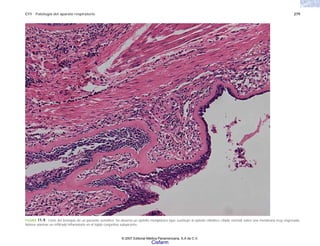

FIGURA 2-5. Histología de la piel en la esclerodermia, con abundante colágena por debajo del nivel de

las glándulas sudoríparas.